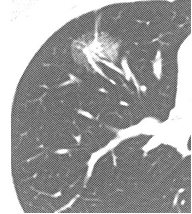

肺がん 検査 金額